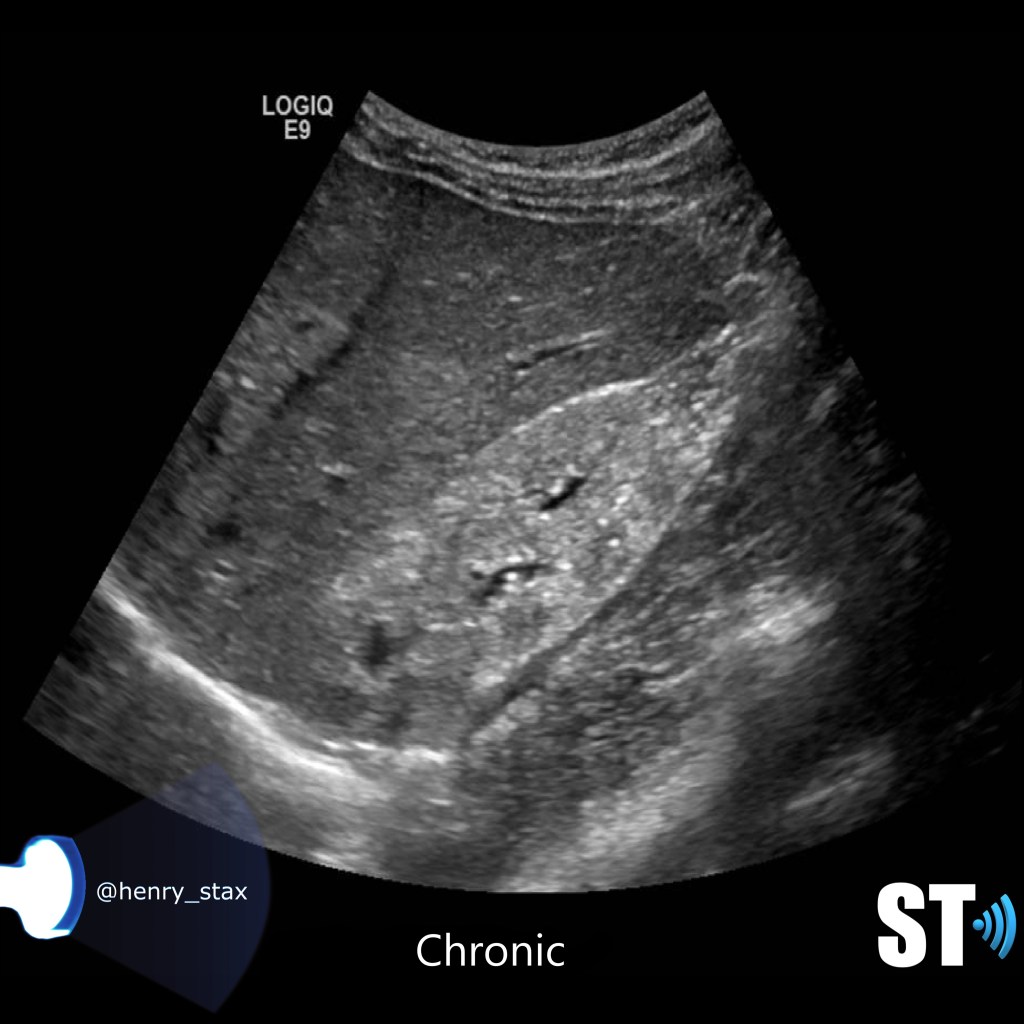

Chronic Pyelonephritis

Chronic pyelonephritis can present as a focal scar from a healed pyelnophritis in the form of focal cortical thinning, If the inflammatory process is diffuse the kidney will be atrophic and scarred.

For our purposes we need to tell whether the kidneys are hyperechoic or not, also is the corticomedullary (cmd) differentiation preserved or is it lost, this can give you clues as to the chronicity of renal parenchymal disease. If the cmd is easily seen it may suggest a more acute process, whereas chronic disease will usually show echogenic and atrophic kidney with little to no differentiation of the cortex to medulla